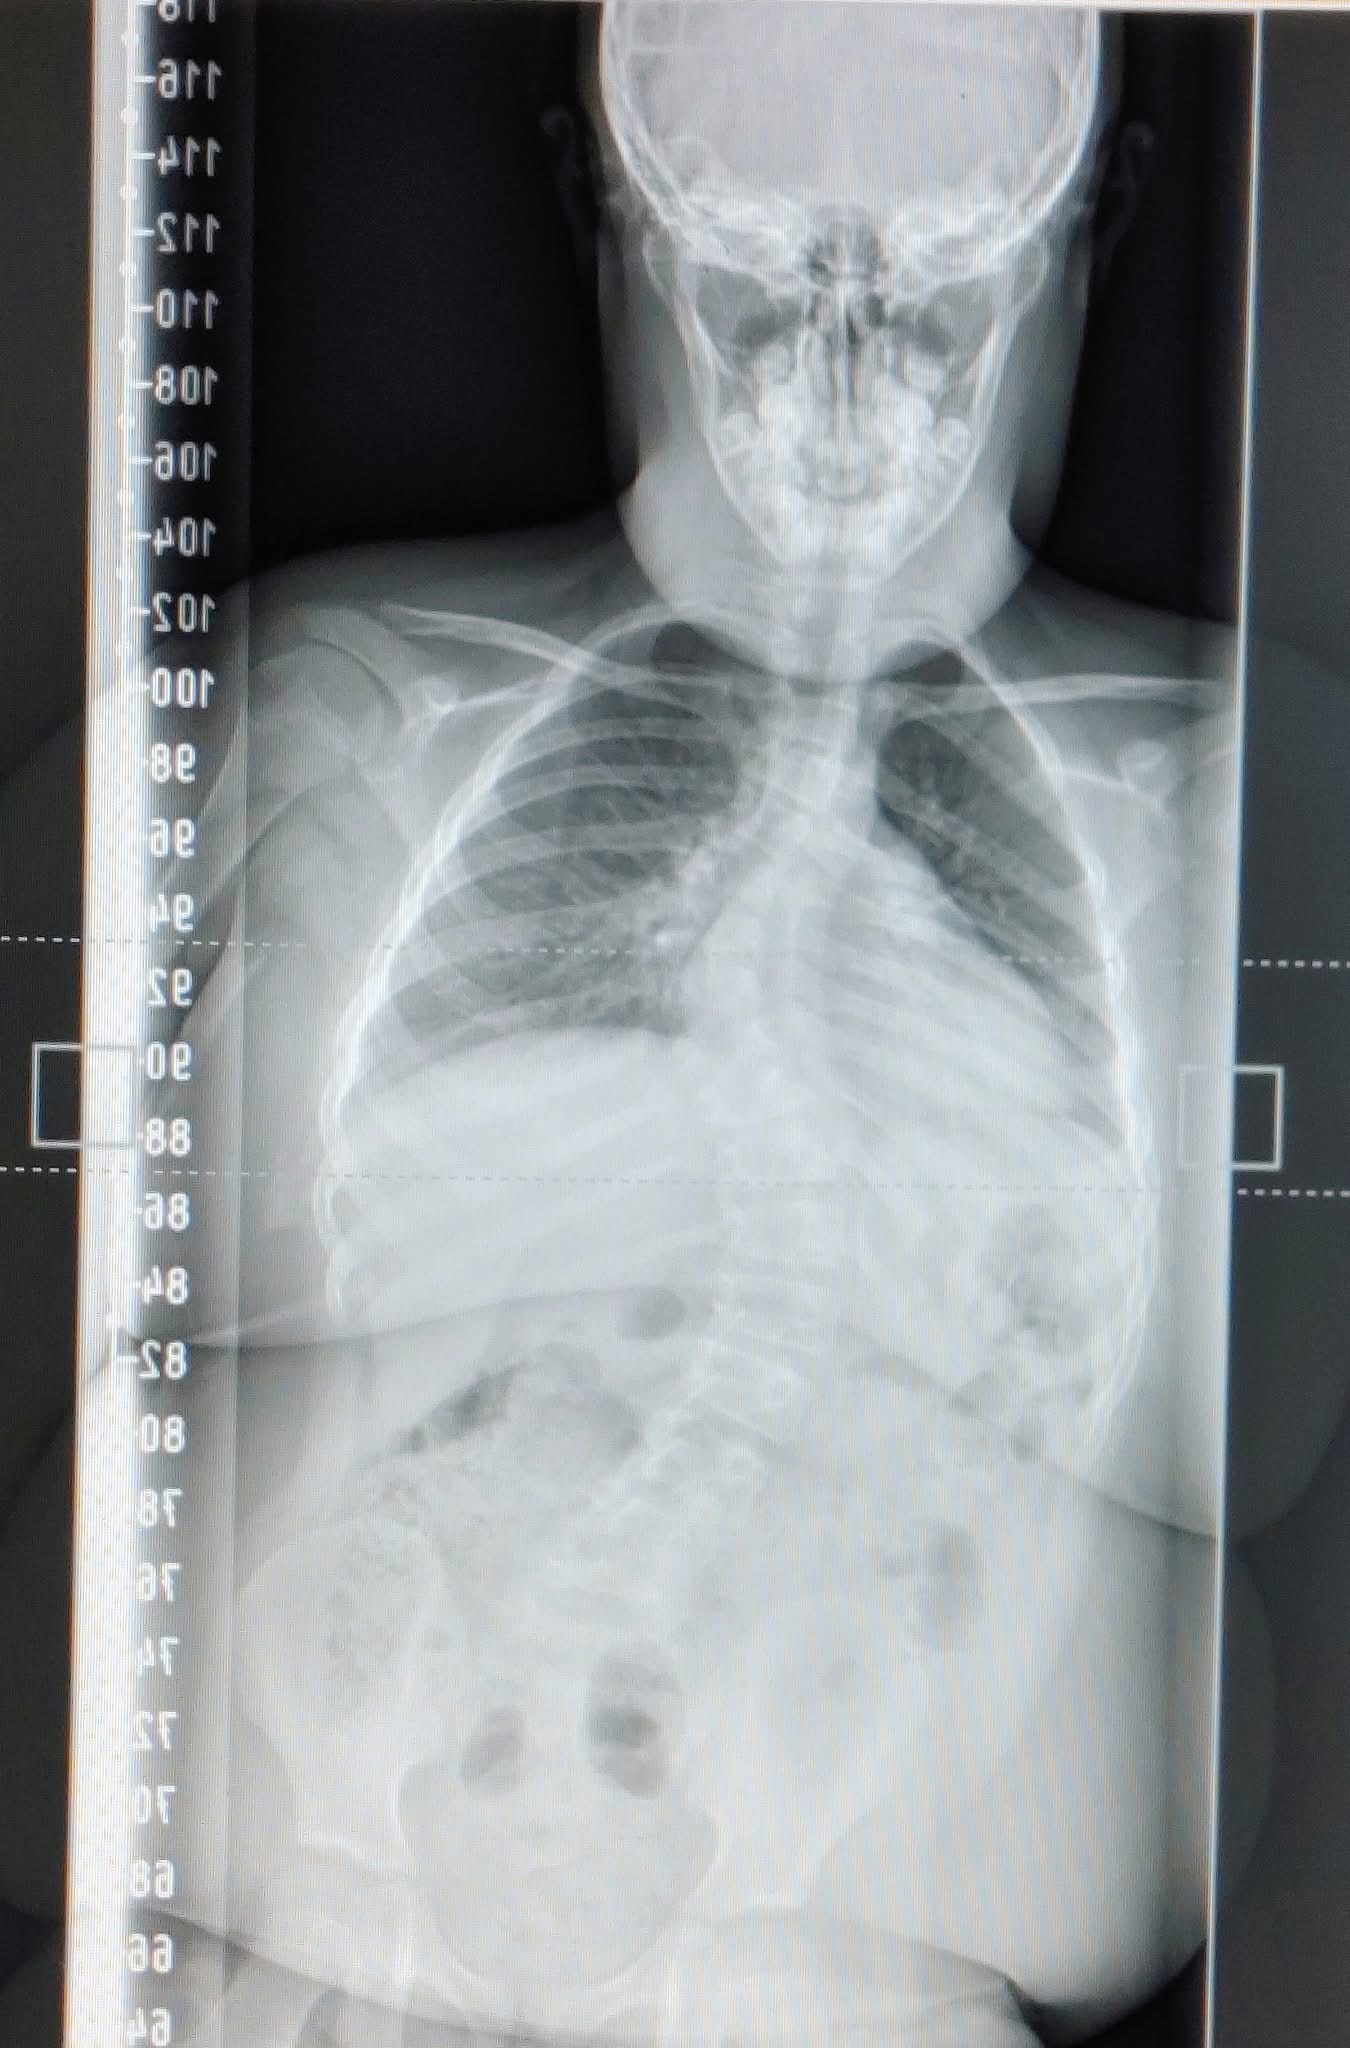

Today (October 7, 2025) is the big day. I'm both happy and terrified. My boy Aiden goes in for his life changing spinal correction surgery at KGH. I will be staying in Kingston for up to two weeks to be there with him through every moment. This is huge. It's a huge step forward for my little guy and I'm trying so hard to stay positive but I'm actually freaking right out. He will be out of school for a minimum of 6 weeks and possibly a lot longer depending on how it all goes. I've been pretty quiet about it all because I've just kept it in the back of my mind because it's scary and upsetting for me to talk about it. The full recovery time is up to a year and requires a bunch of follow ups and just so much stress on this little guy. I just hope he's not in too much pain..

#Scoliosis